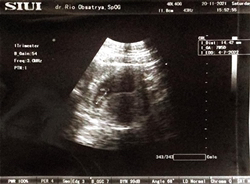

Assamualaikum bunda ? bun disini ada yang hamil 6week ☺️ shere dong bun hasil usg nya ☺️ soal nya saya lagi hamil 6week pas di usg cuman terlihat kantung nya aja ☺️ apa it wajar bun ☺️☺️

Sama bunda aku jg lagi hamil 6wek usg baru keliatan kantung aja, di suruh periksa lagi 3 minggu lagi... Aku sempet galau juga, tp kata dokter itu wajar bun.

Sy 5w wktu USG pertama kali baru kantung jg. Skrg uk 10w nnti tgl 16 baru disuruh balik lagi sm dokternya yg pntg sehat gada flek inshaa Allah baik2 aja bun...

Ini waktu usia 5w lebih. Masih keliatan kantong aja, ukuran kantongnya jg kecil kayak 4w. Tp alhamdulillah sekarang udah masuk 35w, dedeknya insyaallah sehat

Sma bun, aq bru kliatan kntong doang, nnti 8week bru kliatan sma ada detak jntung nya, rutin mnum vitamin yg dkasih dokter aja sma klo bisa mnum susu hmil

setauku kalau masih segitu sampai 8w ya masih keliatan kantungnya aja. nanti udah 10w atau 12w baru keliatan dede utunnya didalam kandung bund😊

Aku wkt itu 7week udh keliatan kantung&janin karna aku transvaginal mom...mungkin kalo usg luar sama keliatan kantung atau hanya titik aja

wajar kok bun. saya kmren usia 5week jg masih kantungnya aja. kosong plong gitu. 😂 usia 8week baru deh kelihatan "isinya" 😂

Wajar bun..😁 Lihat ini sy 9 week usg pake yg trsnsvagina.. Soalnya klo dr perut gk kelihatan jelas